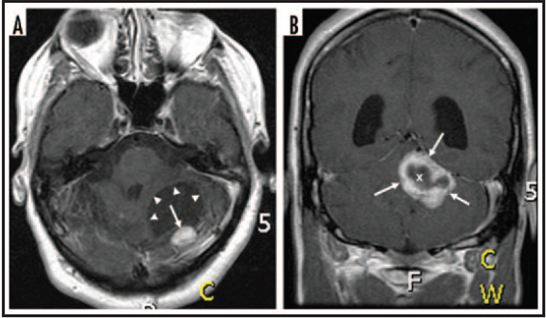

Hình 1: Các vị trí thường gặp của hemangioblastom thường gặp trên lâm sàng.

(A): Hemangioblastoma vùng tiểu não trên hình ảnh cắt dọc và cắt ngang của MRI sọ não.

(B): Hemangioblastoma tái phát ở vùng hố sau trên MRI sọ não và phim chụp mạch não (DSA).